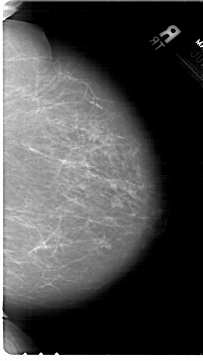

A_1567_1.LEFT_CC

LEFT_CC LINES 6871 PIXELS_PER_LINE 3841 BITS_PER_PIXEL 12 RESOLUTION 43.5 OVERLAY